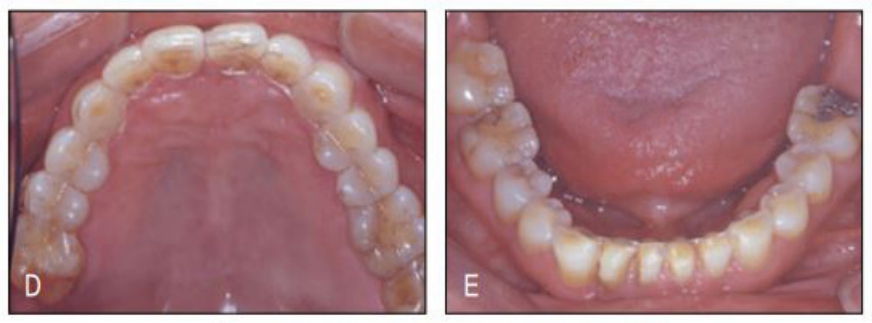

지난 일년 전 하악우측 측절치의 치주 및 근관치료 중 갑작스럽게 치아가 전위되면서 원심부에 공간이 발생한 환자로, 보철을 위해서는 공간재분배가 불가피하여 교정 치료를 위해 의뢰된 환자였다. 하전치부는 교모와 함께 정출이 나타나 이론적으로는 intrusion 후 보철이 필요하지만 환자는 공간재분배라는 간단한 교정치료 조차 받기를 주저할 정도이어 치료계획에 넣지도 않았다.

하악의 공간외에 상악정중부에도 치주질환으로 인한 공간이 있어 치료시 하악 상악같이 할 것을 권유하였으나 환자는 보철을 위해 꼭 필요한 하악에서의 교정만 하는 것으로 하고 상악 치료는 거부하였다. 후에 알게 된 사실이지만 환자가 상악교정을 거부한 이유는 장치의 노출 때문이었다. 교정 장치가 보기 싫어서가 아니라 “나이 들어서 교정치료를 받는 것이 민망해서”라고 하였다. 아직도 많은 이들이 교정은 심미목적으로만 치료받는 것으로 잘 못 알고 있고, 이에 대한 계몽이 필요하다는 것을 본 증례가 여실히 보여주었다.